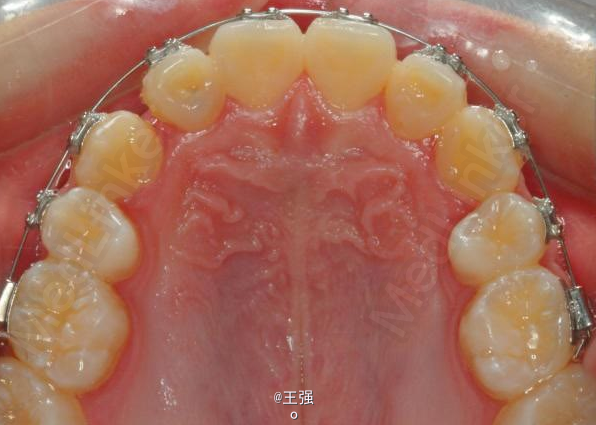

在临床上,我们常常会遇到亚类病例,对于亚类病例,有时需要不对称拔牙,常见的不对称拔牙方法有:上颌对称,下颌数目对称但是位置不对称。还有上颌对称,但是下颌数目不对称。其目的就是为了取得尽可能理想的尖窝对应咬合关系 该病例右侧是中性关系,左侧是中性偏远中关系,上颌中线正,下颌中线左偏约1mm。左侧磨牙关系距离中性关系约差2mm左右。如果采用对称性拔除下颌左右四,我们面临的问题是,一、如何保证矫治后上下中线一致,二、如何保证左侧磨牙关系矫治后为中性关系。治疗过程中势必会用到不对称牵引。我个人认为除非是功能性的因素,矫治过程中最好不要用不对称牵引。 关于中线和磨牙关系的问题,我认为应在矫治计划制定时就应考虑到,而不是等到矫治第三阶段所谓精细调整阶段再来解决。事实上到了这个阶段采用了不对称的牵引,即使暂时取得了中线对齐的矫治目的也是不稳定的。 这个病例,用了不对称的拔牙,右下拔四,左下拔五。下颌牙齿在漂移的过程中(几乎没有外来力量),下前牙自然就会向右比向左多漂移一些,中线在下颌还没有开始矫治时就对齐了,左下六因没有五的存在,自然就向近中多漂移一些,和上颌六形成中性关系。接下来的矫治就会非常简单,而结果自然也非常稳定。